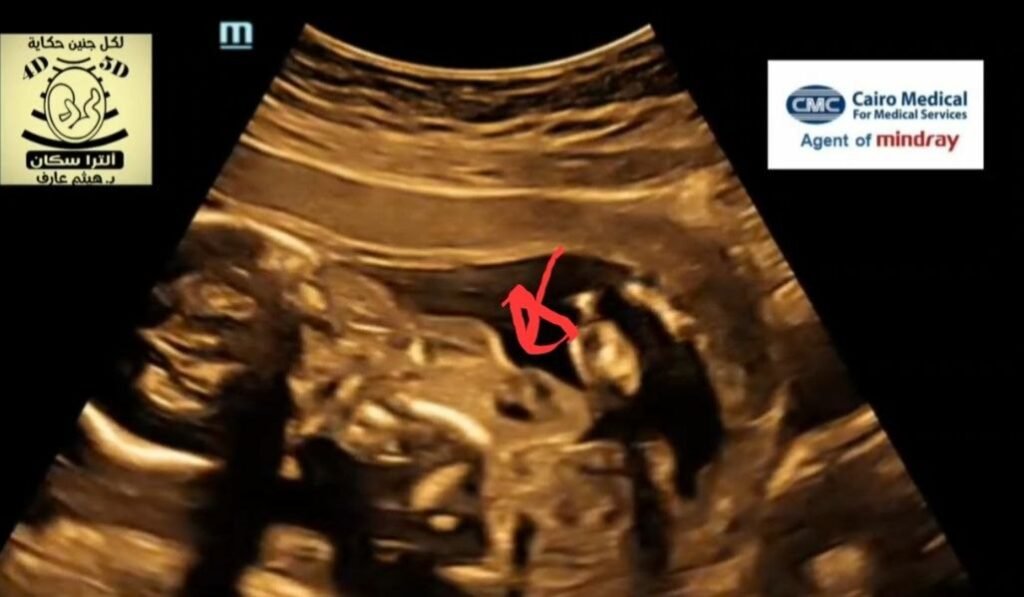

Ectopia cordis fetal ultrasound

Ectopia cordis results from the failure of lateral mesoderm migration into the midline. Some forms may be the outcome of amniotic band syndrome 11.The four main ectopic positions are:adjacent to the thorax: ~60%abdominal: 15-30%thoracoabdominal: 7-18% cervical: ~3%AssociationsEctopia cordis may occur as an isolated malformation or associated with a larger category of ventral body wall defects that affect the thorax, abdomen, or both.Individual associationsVentricular septal defect and tetralogy of Fallot are the most common intracardiac defects. Omphalocele is the most common abdominal wall defect.Syndromic associationsA well-known association is pentalogy of Cantrell, which comprises of 1:ectopia cordisomphalocele (typically supraumbilical)congenital diaphragmatic herniasternal cleftcongenital heart disease